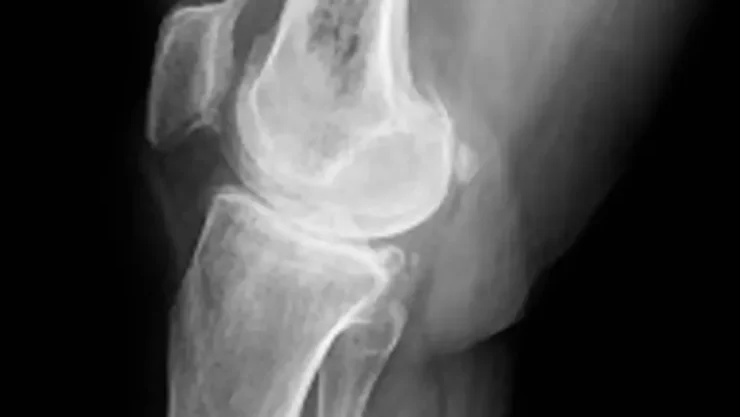

RZ NOTICIAS, MADRID.- El osteosarcoma -un cáncer óseo agresivo que afecta sobre todo a niños y jóvenes de entre 10 y 20 años- esconde una enrevesada genómica que dificulta su estudio, por eso las terapias no han cambiado en décadas. Ahora un equipo de científicos españoles ha logrado un avance fundamental: explicar la complejidad biológica de este cáncer.

Por ahora, el tratamiento de este tipo de cáncer exige quimioterapia, cirugía o amputación. Además, el osteosarcoma tiene el potencial de expandirse a otros órganos, principalmente a los pulmones.